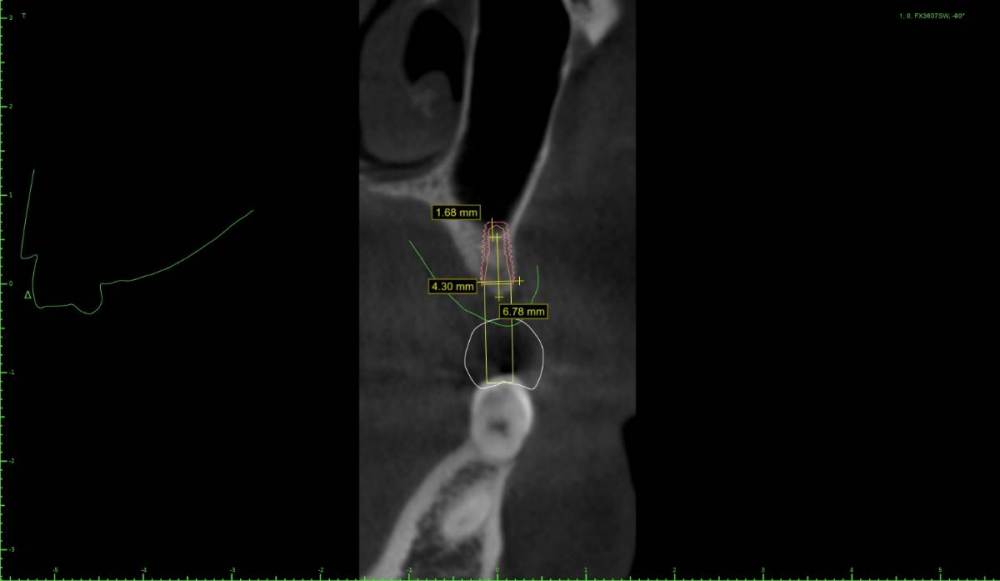

Женька Опубликовано 22 мая, 2021 Поделиться Опубликовано 22 мая, 2021 Дабы не захламлять тему про "мильён вопросов" я всё же создал свою. Итак, я получил оттиск верхней челюсти, отлил модель и перевёл в stl. Мои остеотомы застряли где-то в Пуяне и постучать нечем. Но в теме с мильёном вопросов пришли к выводу, что и зсл не нужен, только нкр. Что под рукой: даск с его фрезами для зсл, мембрана еволюшн, микс апатоса и только нитки, чтобы всё это зафиксировать. Также есть вариация имплантата суперлайн 2 (1.5мм полированной шейки и 5.5 шероховатой) или же полностью шероховатый суперлайн 1 с полированной фаской (3.6*7мм), но макродизайн менее агрессивный. Также будет сделан шаблон под пилотное сверление. Вот такие варианты получились. Вопрос, можно ли будет сделать маленькую нкр с имплантатом имеющим 1.5мм полированную шейку (как я понимаю - нет)? Ссылка на комментарий

Женька Опубликовано 31 мая, 2021 Автор Поделиться Опубликовано 31 мая, 2021 @Карен Аванесов я вот тоже склоняюсь к суперлайну первому неагрессиному...и маленькой НКР с прижатием мембраны швами к надкостнице. Ссылка на комментарий

Женька Опубликовано 17 июня, 2021 Автор Поделиться Опубликовано 17 июня, 2021 Как вы наверное уже догадались я не осилил этот кейс. Точнее осилил, но не как планировал изначально. Сделал маленькую сосиску, уже прогнозирую, что мало что там вырастет у меня. Пытался собрать ауто, сначала скрёб бузеровским распатером, потом решил сделать «ложе» для имплантата и забрать кости там. Насобирал мало конечно же. Сделал какое-то подобие штайгмановского лоскута кмк, хотя наверное это не так. Подшил мембрану к надкостнице, хотел чтобы надкостница была в нахлест на мембране, вышло «в стык». Утрамбовал апатос, подшил под нёбный край. Плотненько получилось, даже понравился вид ( а фото забыл сделать) Натянул лоскут, хотя прежде мобилизовывал хорошо как показалось. Снова мобилизовал, ушил. Уже жду когда это развалится. Соотношение ауто/ксено примерно на уровне 80/20(думаю даже меньше). Думаю, что надо было дистально лоскут ещё на зуб продлевать. Но есть и хорошие новости, я кажется понял, каким пациентам я буду отказывать в лечении... ну и лоскут не порвал, это уже уровень для меня. Ссылка на комментарий